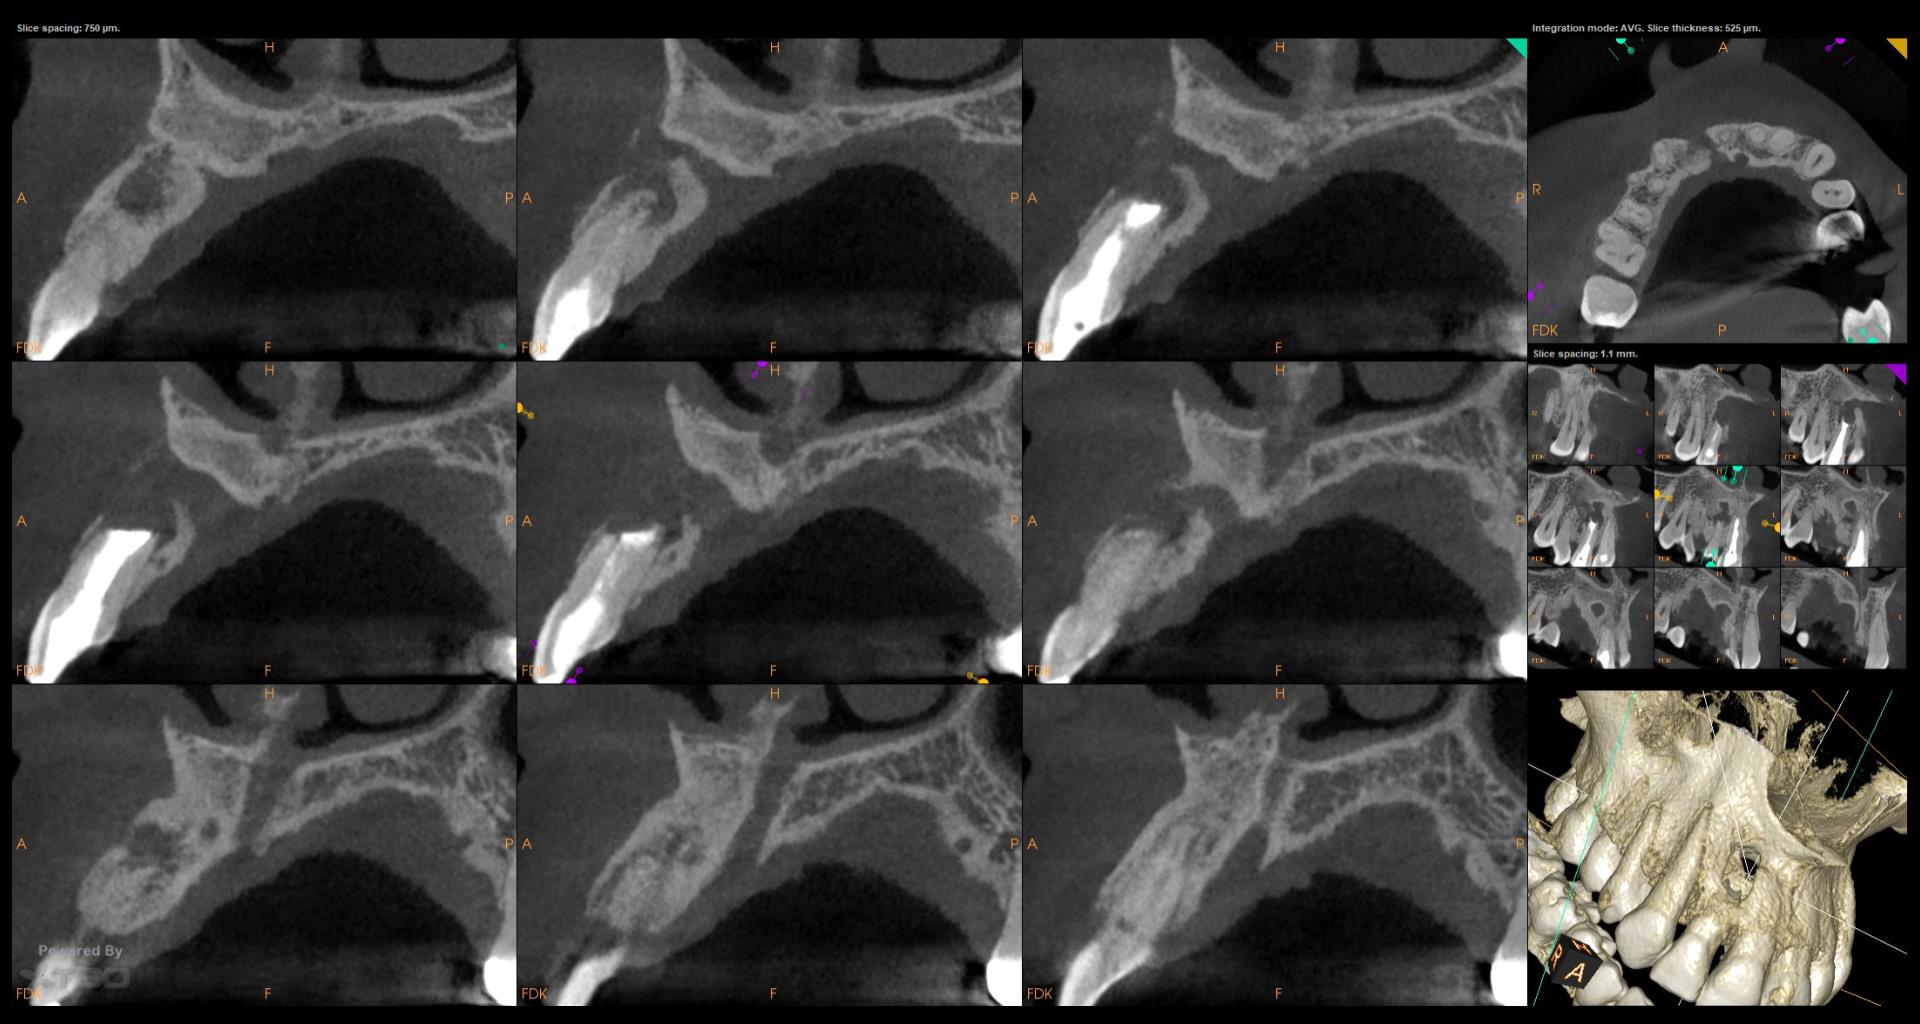

Do you have the previous review x ray s,

Interesting case, Gary. Asymptomatic, but 17-year recalls are crucial! Maybe a bitewing radiograph to check for interproximal caries? A preventative approach avoids future, more involved treatment. Reminds me of needing a winning strategy in Retro Bowl to avoid penalties later on!